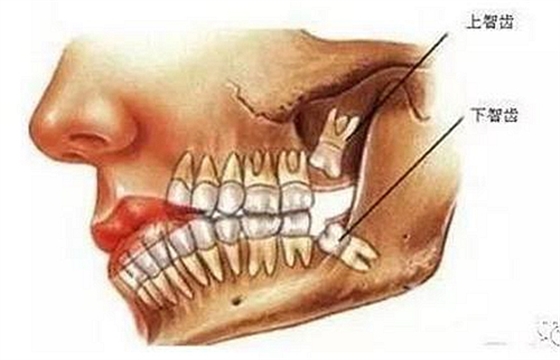

智齒也稱智慧齒、是人類的第三磨牙,隨著遺傳基因的不同智齒一般會在16-30歲之間長出,也是人一生中最后長出的牙齒,所以它最靠近喉嚨,因為此時期的人們心智比較成熟而得名。從門牙數往里第八顆,一般成年后長出來。由于人類進化,這顆第三磨牙失去了作用。逐漸退化,限制于空間,有些長歪了,有些頂著前面的牙齒,有些埋伏在牙槽骨里出不來。

智齒周圍是牙槽骨,前面緊挨著第二磨牙,智齒下方大約兩三毫米遠有一下頜神經管,這神經主要是下頜牙齒及下唇部位的知覺神經,一旦斷了,就會失去知覺。

根神經線位置千變萬化,有些離智齒牙根很遠,有些很近,有些甚至穿過智齒根部。